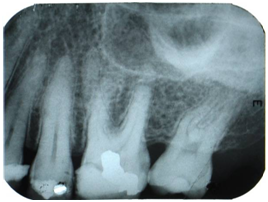

Figure 3 Obturation of the four root canals.

For irrigation it was used a fresh solution based on sodium hypochlorite 1% (Phormula Ativa, Recife, Brazil). The actual working length (AWL) was determined at 1 mm short of the radiographic apex. For the irrigation of the root canals it was used the system with syringe FCF (FCF, São Paulo, Brazil) of 3 mL with needle 27G long (Injecta, Diadema, Brazil). The irrigation was performed at the beginning of the instrumentation, between the changes of the instruments and at the end of biomechanical preparation. All root canals were instrumented with the ProTaper Universal™ rotary system using an electric motor X-Smart (Dentsply, Maillefer, Ballaigues, Switzerland) at a constant speed of 300rpm. Initially, the instrument SX was introduced into the 2/3 of the AWL, then the dental file S1 was used in 4mm short of the AWL, then the instruments S1 and S2 were introduced in the AWL and, finally, it were used the dental files F1, F2 and F3 in AWL. At the end of the preparation, there was an irrigation with 1mL of 17% ethylene diamine tetra acetic acid (EDTA) (Biodinâmica, Paraná, Brazil) during 1 minute to remove the smear layer, irrigation with sodium hypochlorite 1% and drying of the root canals with points of absorbent paper (Dentsply, Maillefer, Ballaigues, Switzerland). Afterwards, there was the application of calcium hydroxide paste (Calen, SSWhite, Pensilvânia, EUA) as intracanal medication and coronary sealing of the tooth with zinc oxide and eugenol dressing (Biodinâmica, Paraná, Brazil). After 7days, the medication was removed using Flexofile, and it was made an abundant irrigation with sodium hypochlorite 1%; it was made the drying with points of absorbent paper (Dentsply, Maillefer, Ballaigues, Switzerland), the cone fit radiograph was performed followed by filling with gutta-percha main and accessory cones (Dentsply, Maillefer, Ballaigues, Switzerland) and with endodontic cement MTA Fillapex (Angelus, Paraná, Brazil), using the lateral condensation technique. After radiography for visualization of lateral condensation, it were made the vertical condensation of the material with condenser Paiva nº 3 (Golgran Indústria e Comércio de Instrumentos Odontológicos Ltda., Pirituba, SP, Brazil) and cleaning of the pulp chamber with eucalyptol (Biodinâmica, Paraná, Brazil) (Figure 3). The tooth was provisionally sealed and the patient was referred for restorative treatment.

The present work reported a case of endodontic treatment on a left maxillary first permanent molar with four roots, being: one distopalatal, one mesiopalatal, one mesiobuccal and one distobuccal, and four independent root canals. The palatal roots were classified as type I9 and the palatal canals have been classified as type I.15,21